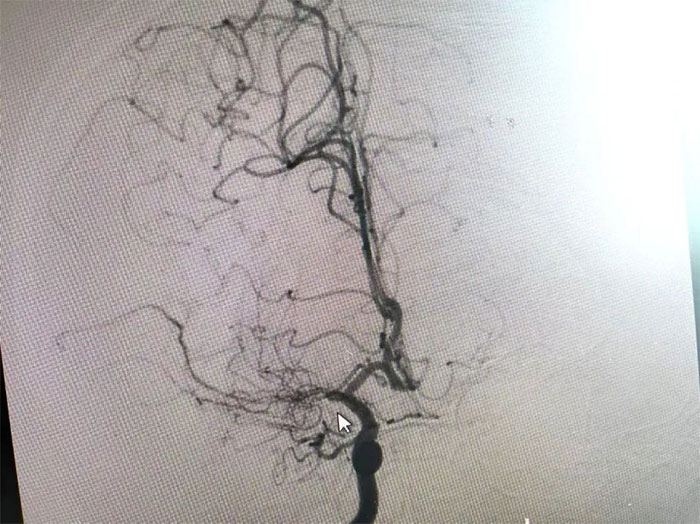

在与患者及家属充分沟通后,李振并主任为周先生展开了DSA(数字减影血管造影)检查。

在检查中发现,周先生右侧大脑中动脉M1段闭塞,可见烟雾状异常血管网生成;左侧大脑中动脉M1段重度狭窄(约70%)。符合烟雾病的典型影像学特征。

▲ 检查发现烟雾状异常血管网

烟雾病又名Moyamoya病,脑底异常血管网,是一组以Willis环双侧主要分支血管(颈内动脉虹吸段及大脑前、中动脉,有时也包括大脑后动脉)起始部慢性进行性狭窄或闭塞,继发出现侧支异常的小血管网为特点的脑血管病。因脑血管造影时,呈现许多密集成堆的小血管影,似吸烟时吐出的烟雾而得名。